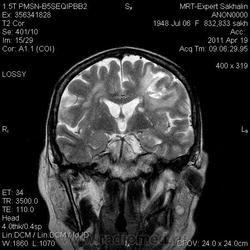

Это демиелинизирующий процесс, острая стадия, причем с геморрагическим пропитыванием в центре пораженных участков. В принципе, соответствует тяжелому рассеяному склерозу, хотя может быть и геморрагическая форма ОДЭМ. Также могут быть мозговые проявления системного васкулита: надо знать анамнез.

На фоне ДЭП изменений МР-картина ОНМК по ишемическому типу в бассейне ЛСМА с участками геморрагического пропитывания. Аналогичный участок но в более поздней фазе в задних конвнкситальных отделах правой теменной доли.

О.С., я согласен, что контрастирование нехарактерно для ОНМК, ведь в подострую стадию инфаркта наблюдается, как правило, гиральный тип усиления. Плюс, на ОНМК непохоже то, что поражено почти только белое вещество, а кора интактна. И потом, при такой локализации инфаркта обязательно должна быть яркая клиника, и уж никак не только "головная боль".

А средний мозг ?Там тоже очаги гиперинтенсивного по Т2сигнала.

Что касается снимочков мне кажется что зона патологического сигнала в левой гемисфере можно расценить как подострую стадию ОНМК с геморрагическим пропитыванием, справа как последствия ОНМК. При чем множественные очаги скорей всего как проявление ХМНК. И обязательно рекомендовать контрольное МРТ в динамике . Если это действительно ОНМК на фоне лечения отек уйдет и будет формированиться зона кистозно-глиозных изменений, а если отек будет нарастать значит надо думать о объемном процессе.

Как вариант хочу предложить на рассмотрение грибковое поражения головного мозга или токсоплазмоз. В таком случае полностью укладывается изменение сигнальных характеристик и на нативе и на постконтрастных сканах. Можно проверить на иммуносупресивные состояния, на наличие грибкового эндокардита (Узи сердца).

На опухоль не тянет. Для инфаркта и банальной гемморрагии не характерен тип накопления контраста на мой взгляд.

На динамике видно что это был действительно ОНМК - сомнений нет, данных за объем не вижу.